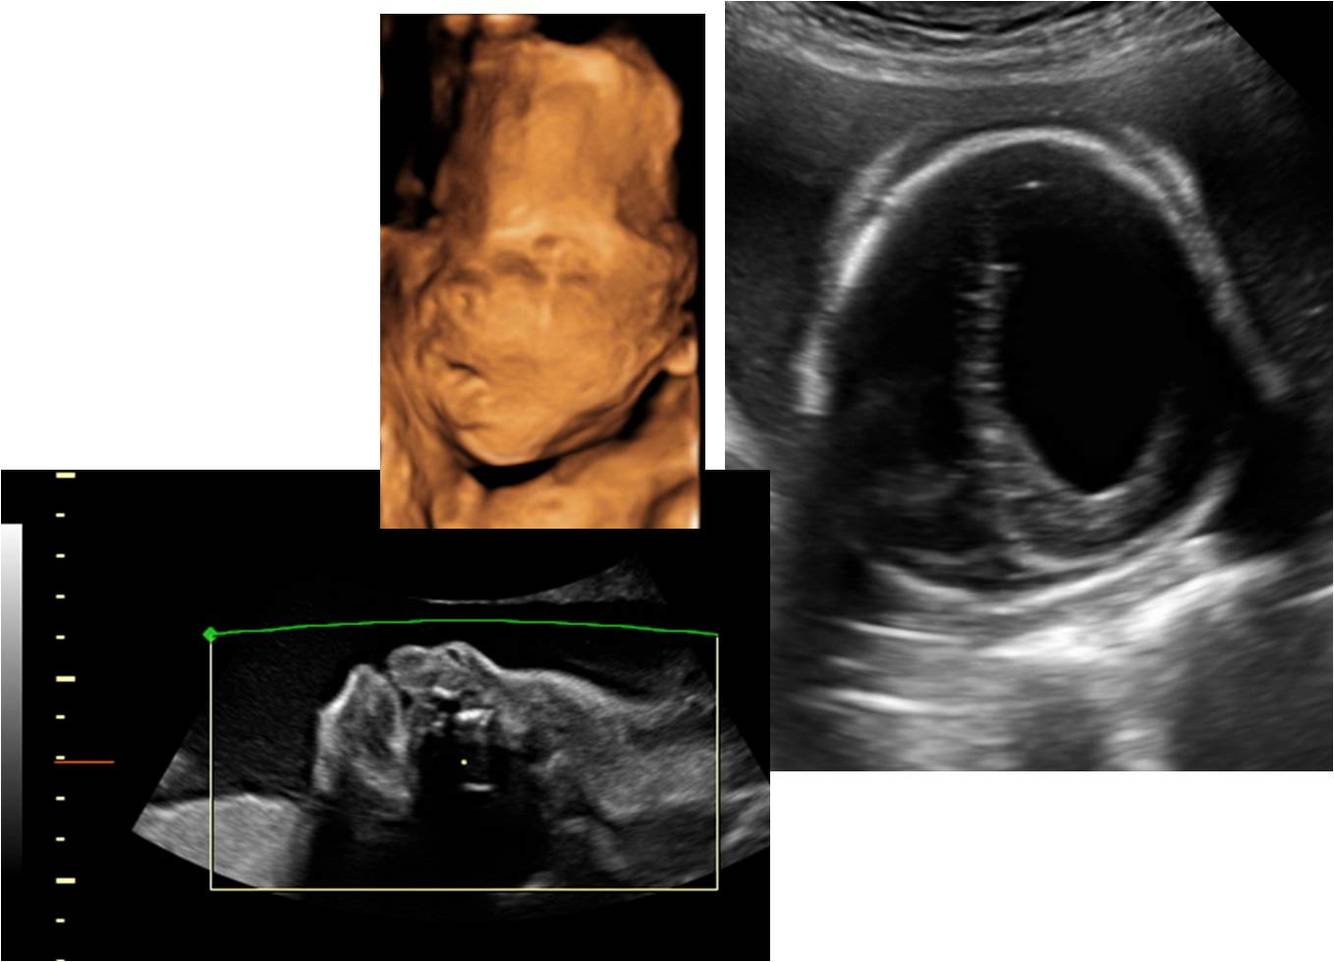

Hydrocephalus

Hydrocephalus is a buildup of fluid inside the skull that leads to brain swelling.

Cloverleaf deformity

Severe coronal craniosynostosis.

Brain forms in a vertical direction.

Associated hydrocephalus.

Choroid Plexus Cysts

Holoprosencephaly